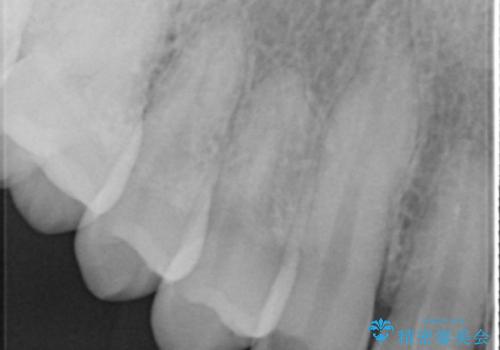

- 「前歯に穴が開いたから診てほしい」とのことで来院。

全体的に歯と歯茎の間境目が白く、右上の前歯は穴が開いてしまっていました。

インレーでの修復はできない場所であるため、セラミッククラウンでの治療になりました。

全体的に歯の脱灰が目立っており、右上の犬歯のみ状態が悪く穴が開いてしまっていました。

審美的にも優れるセラミッククラウンで修復し、他の歯も同じ状態になってしまわないよう歯磨き指導をさせていただきました。